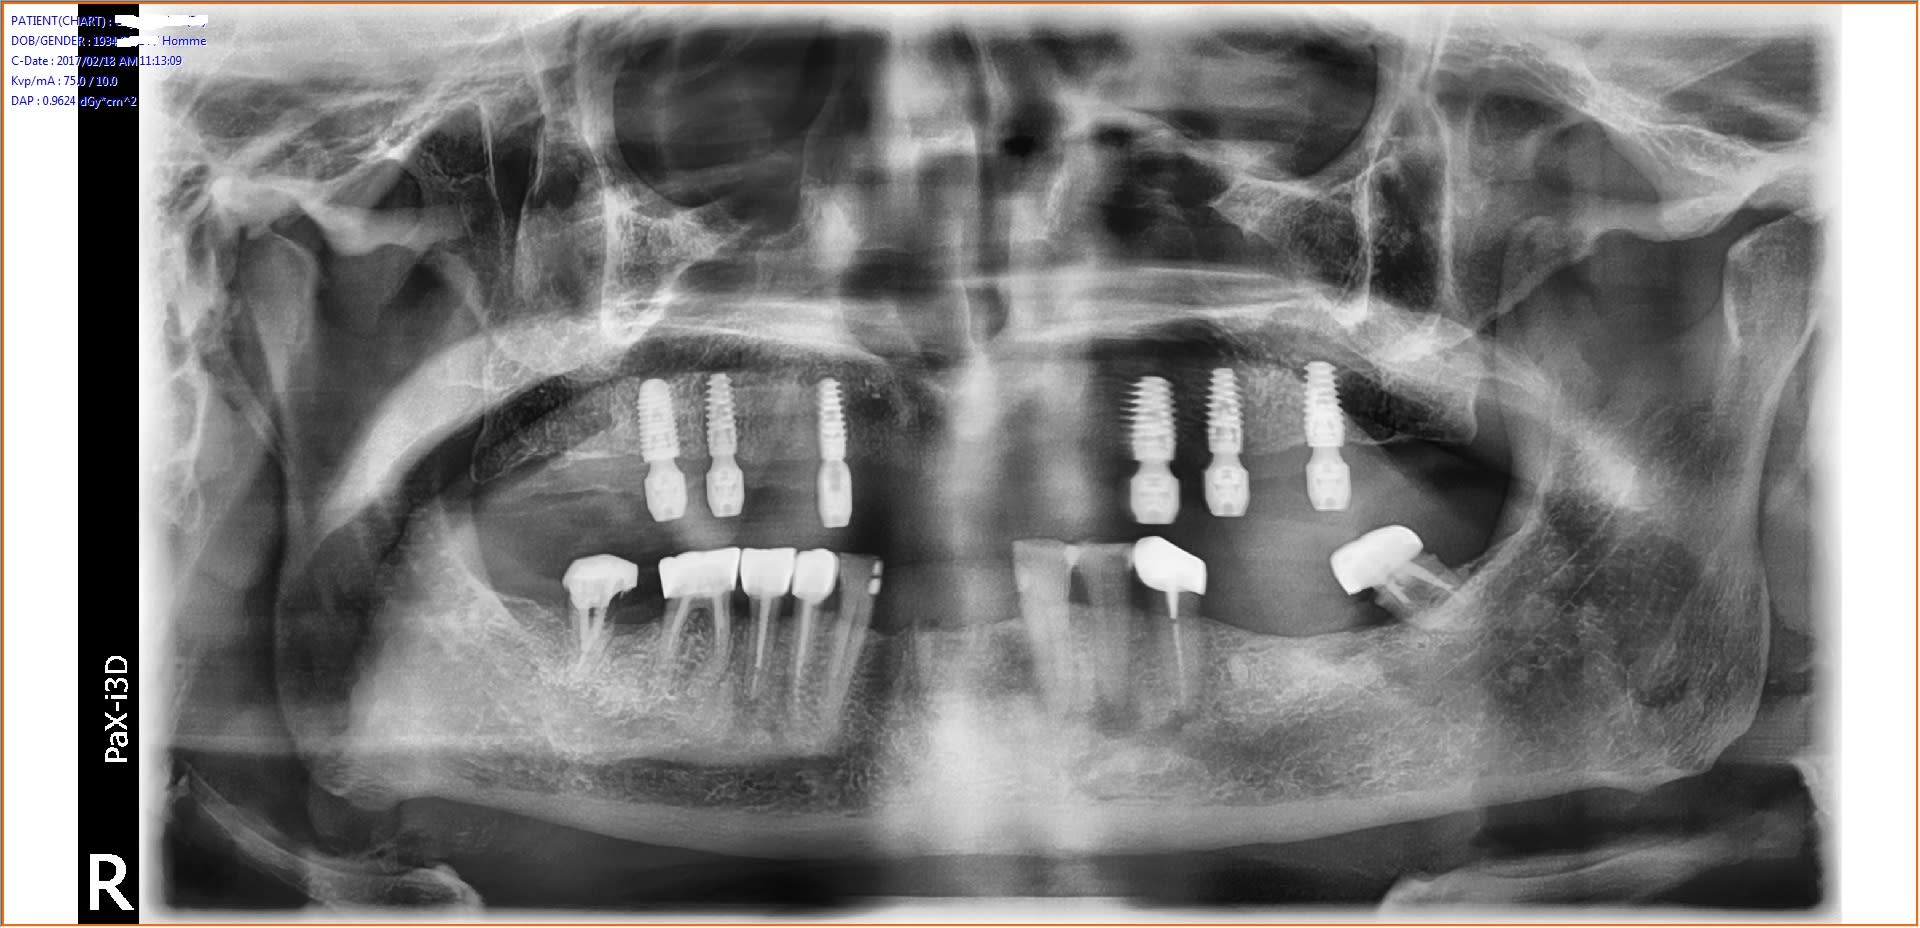

C'était un cas à risque: patiente 49 ans fumeuse depuis x années près d' 1 paquet/jour + prodontite generalisée avec tartre etc. un dentiste lui avait proposé 2 PAC et elle en était malade à l'idée d'avoir des prothèses amovibles et perdre ses dents... Elle aurait du bruxisme la nuit selon ses dires sans pour autant avoir de l'usure importante des faces occlusales. Pour me simplifier la tâche après le det approfondi+ conseils j'ai fait ext des dents max et PAC immédiate en attendant une cicatrisation complète. Entre temps la patiente a fini par arrêter complètement le tabac. J'ai fait un guide avec une DV plus importante que la PAC, qui lui permettrait de serrer moins fort les machoirs par la suite. CBCT avec guide, choix des implants (anthogyr axiom px 4 de diamètre et 10mm de long sauf en postérieur à 8mm et 5,2mm de diamètre.)

Sous forage d'un foret pour tous sauf pour les 2 posterieur j'ai sous foré de 2 diamètre (4mm). Je n'ai pas utilisé d'osteotomes pour compacter ou faire du summers pour le 1mm final dans le sinus (à peine 8mm de hauteur d'un côté) malgré tout je n'ai eu un blocage que à 15N pour les 2 deniers implants larges. Les autres bloqués à 35N. Les 2 implants du secteur antérieur sont angulés d'environ 20 degrés en vestibulaire pour suivre l'axe de la crête. J'ai aussi légèrement vestibulé l'axe des prémolaires en m'appuyant sur la tolérance d'axe de rattrappage avec les multiunits.

J'ai perdu trop de temps à faire un lambeau d'épaisseur total car je n'ai pas l'habitude mais ca devrait s'accélérer avec le temps j'espère. Pose des piliers MU, sutures simples avec fil 4.0 resorbable, empreinte à l'impregum soft et PEI à ciel ouvert. Pose des capuchons et mordu au silicone à la dv du guide mesuré avec un compas. Antalgiques nvI + celestene 6mg/j pour 3 jours + ATB. A 72h pose du bridge et reglage de l'occlusion. Les sutures sont laissées pour l'instant.